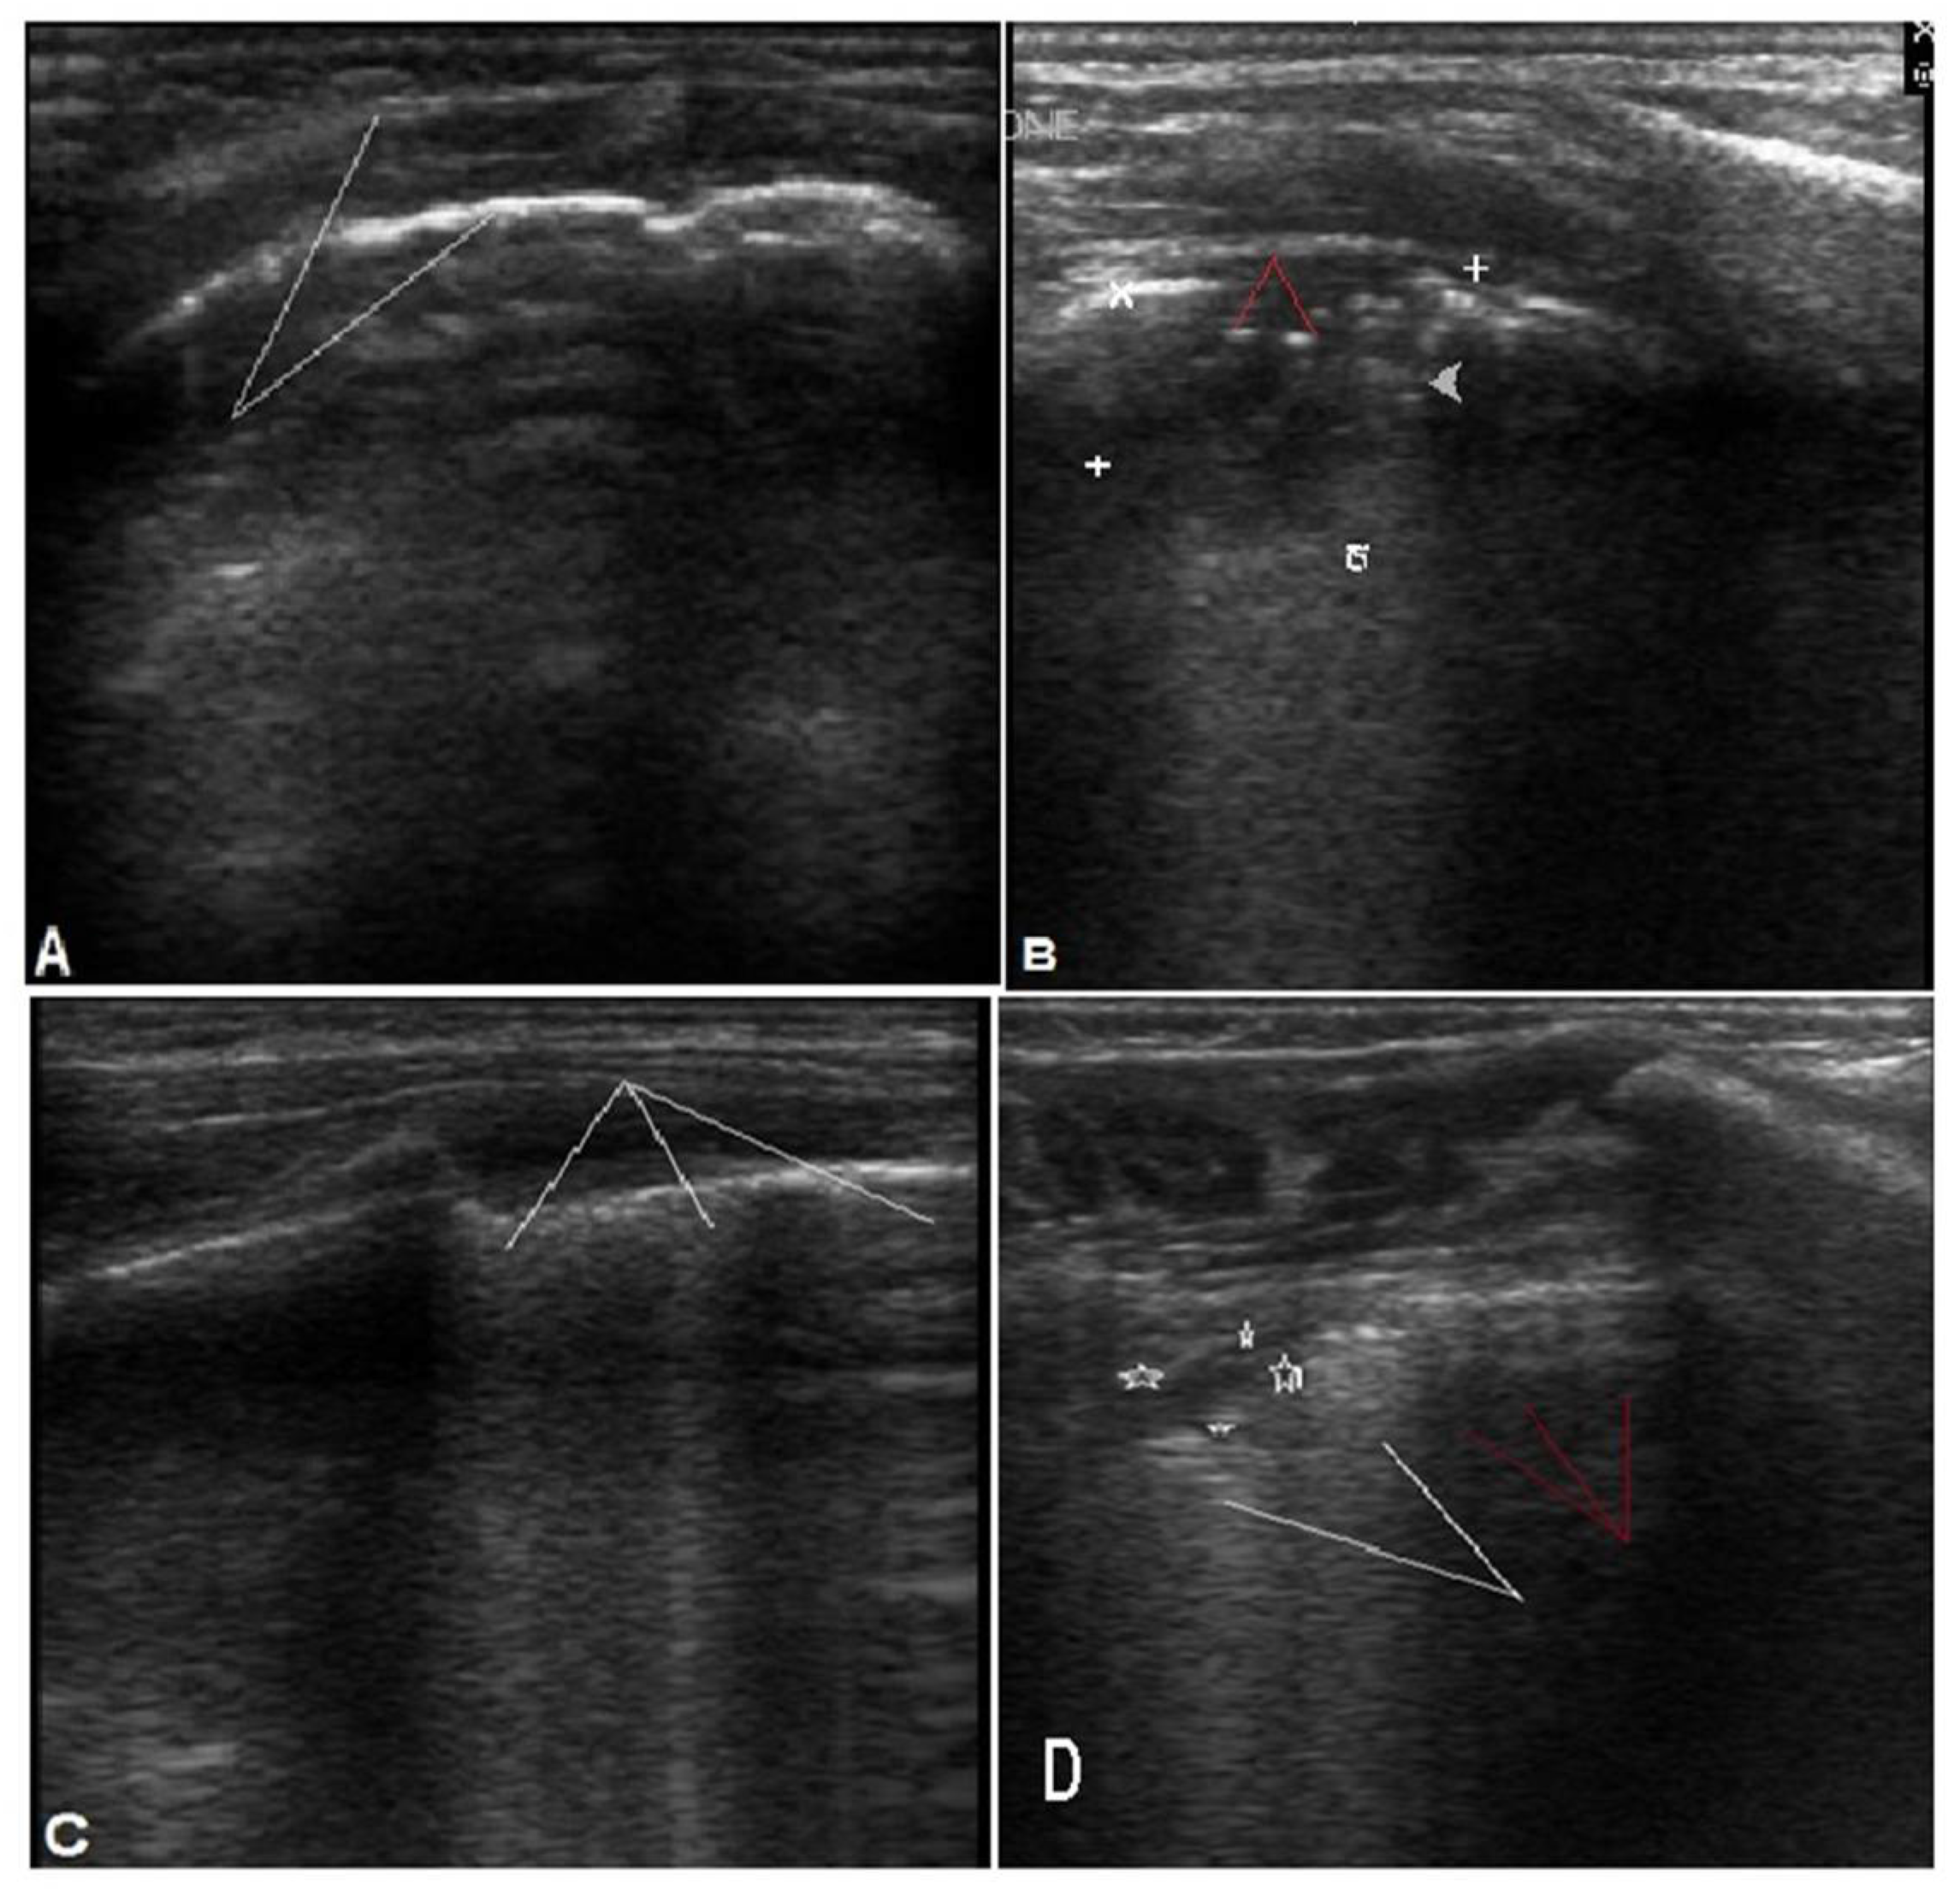

| LUS Findings | ||||

| Pleural line | Regular | 7 (20.5%) | 11 (61.2%) | 0.009 * |

| Disturbed | 27 (79.5%) | 7 (38.8%) | ||

| Subpleural consolidation | >1 cm | 30 (88.2%) | 4 (22.2%) | <0.0001 * |

| <1 cm | 4 (11.8%) | 14 (77.8%) | ||

| Air bronchogram | Yes | 30 (88.2%) | 1 (5.5%) | <0.0001 * |

| No | 4 (11.8%) | 17 (94.4%) | ||

| B-lines | Yes | 4 (11.8%) | 15 (83.8%) | <0.0001 * |

| No | 30 (88.2%) | 3 (16.2%) | ||

| Lung sliding | Normal | 8 (23.5%) | 16 (88.8%) | <0.0001 * |

| Decreased | 26 (76.4%) | 2 (11.2%) | ||